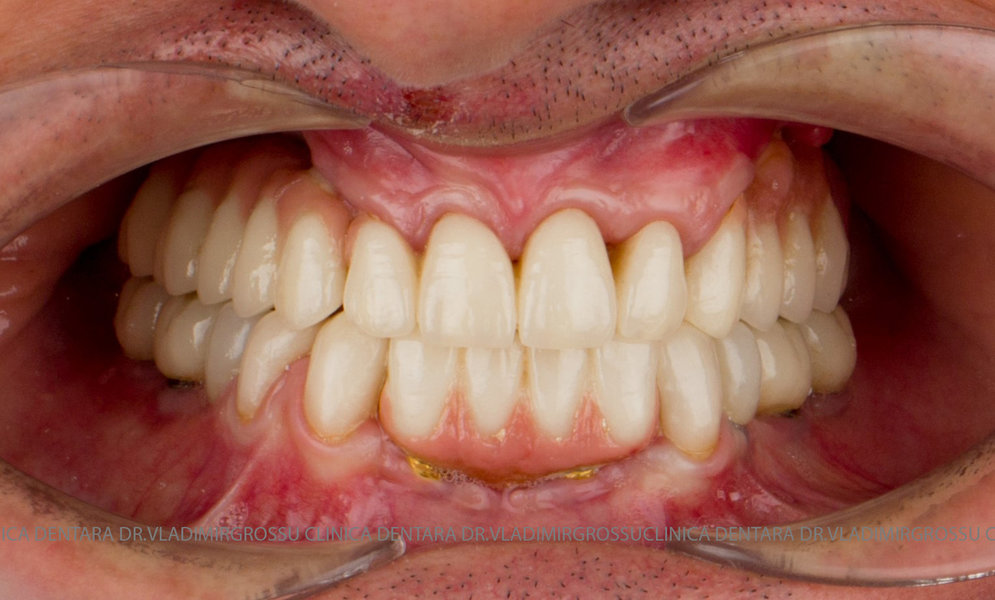

Cazuri clinice conceptul All-on-6